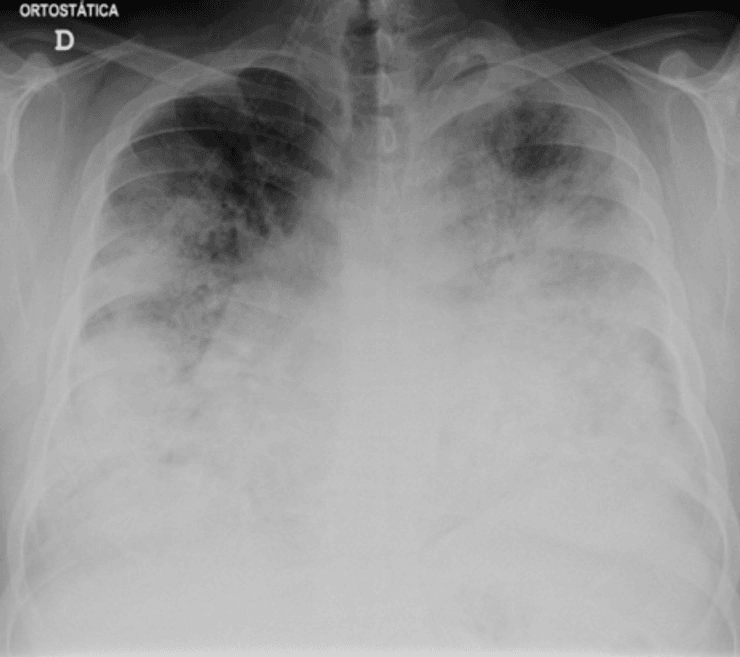

Рентген грудной клетки тяжелого случая легионеллеза при поступлении в отделение неотложной помощи